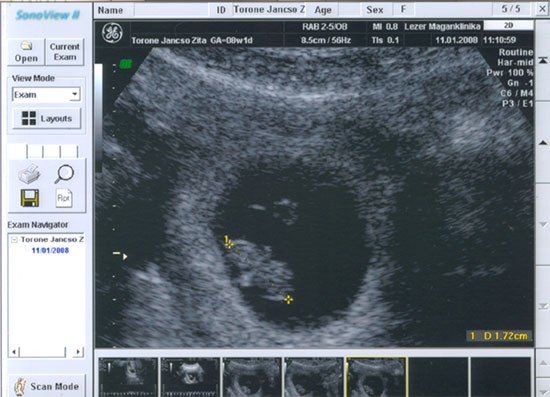

nem látszik pedig nagyon alaposan megnézte!

nem látszik pedig nagyon alaposan megnézte!2008.01.11 16:06